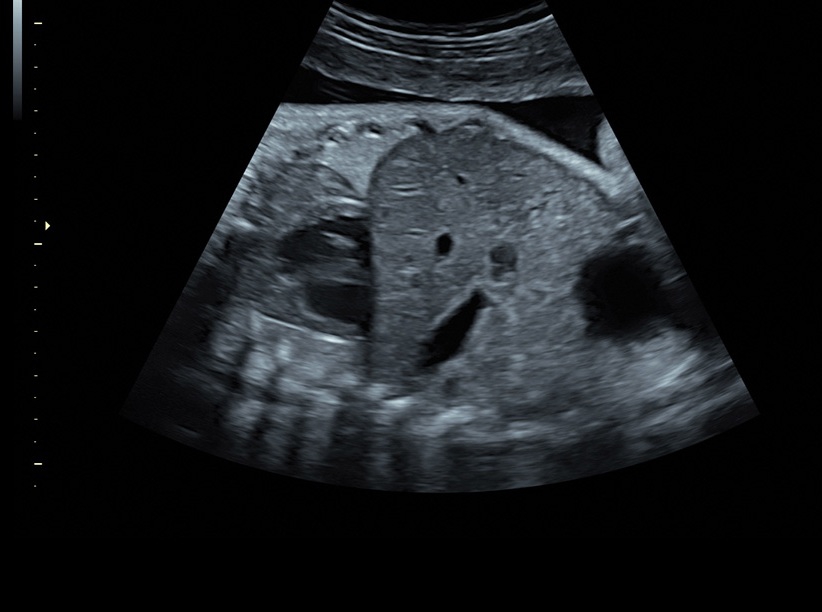

• Сложные инструменты для оценки качества плода: Сканер оснащен инновационными инструментами, позволяющими проводить детальную оценку состояния плода, включая его сердечную деятельность, анатомию и кровоток.

• Технология автоматической фетометрии в 2D режиме (SonoBiometry): Эта технология позволяет автоматически измерять бипариетальный размер, окружность головы, окружность живота, длину бедра и плеча плода, обеспечивая точные и надежные измерения.

• SonoBiometry (автоматическое измерение BPD, AC, HC, HL, FL)